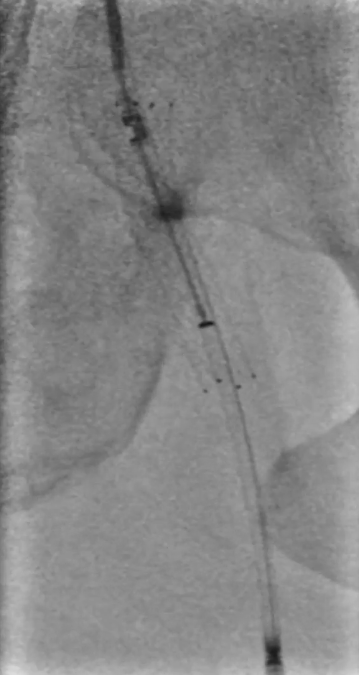

预扩张:先用3mm球囊对病变段预扩张,便于后续器械导入。

保护伞置入:于腘动脉P2段水平放入6mm Spider 保护伞,预防栓塞。

定向旋切:采用新一代Hawk-Plus定向斑块旋切装置进行减容。对于支架内闭塞段,放大图像,确保刀头在可视范围内,反复旋切至接近支架边缘;

对于支架远端病变段,分别采用4个方向各旋切1次,完成初期减容。

器械优势:刀头弧度更大,与血管壁接触面积广,切除效率更高;